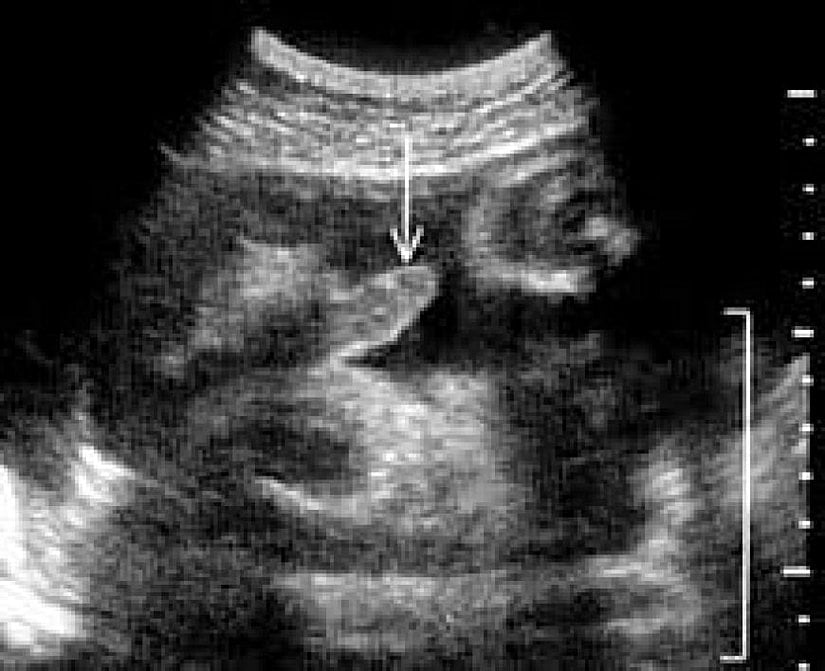

Ana Karnındaki Bebekler de Erekte Olurlar!

Evet, erkek bebeklerin annelerinin karnında ilk ereksiyonlarını yaşadıkları bilinmektedir. Öyle ki, erkek bebekler ana rahminde her saat birden fazla defa erekte olabilirler. Bunun tam olarak neden gerçekleştiği bilinmemektedir, çünkü erkekler normalde ergenlik çağına kadar pek fazla erekte olmazlar. Aşağıdaki fotoğrafta 36 haftalık bir bebeğin ereksiyonu görülmektedir.